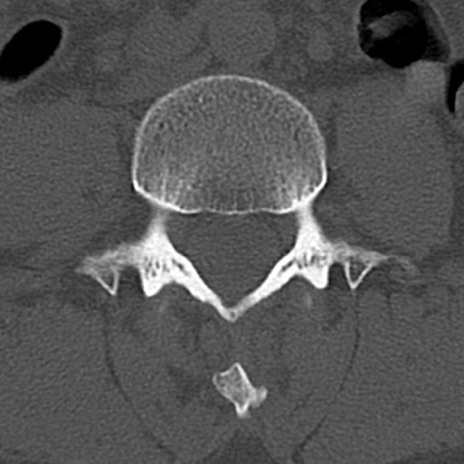

腰椎CT

横断像と矢状断像